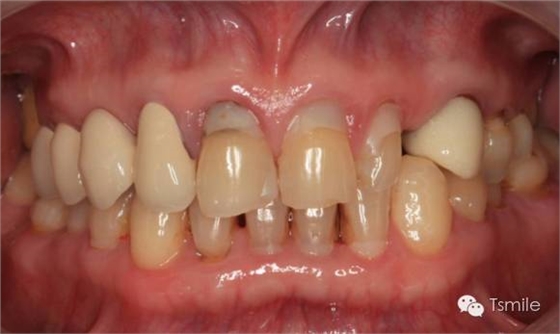

牙列重度磨耗的患者,特別是全牙列重度磨耗的患者,其口腔美觀和功能都受到了嚴(yán)重影響?;颊卟粌H需要口腔美學(xué)重建,還需要口腔功能的重建。

例如面對一個(gè)牙列重度磨耗的美學(xué)修復(fù)患者,我們首先根據(jù)患者主訴和美學(xué)檢查形成美學(xué)設(shè)計(jì),然后通過數(shù)碼圖像表達(dá)美學(xué)設(shè)計(jì)思想,制作診斷蠟型,口內(nèi)制作診斷飾面,更加真實(shí)地表達(dá)美學(xué)設(shè)計(jì)。根據(jù)患者的要求和口內(nèi)試戴情況調(diào)改診斷飾面,最終確定美學(xué)修復(fù)設(shè)計(jì),即最終修復(fù)體的各種美學(xué)參數(shù)。接下來就是美學(xué)實(shí)現(xiàn)過程,在診斷飾面上進(jìn)行精確地牙體預(yù)備,制取印模和工作模型,技師按照最終診斷飾面的形態(tài)、大小和排列制作最終美學(xué)修復(fù)體,最后完成修復(fù)體粘接。